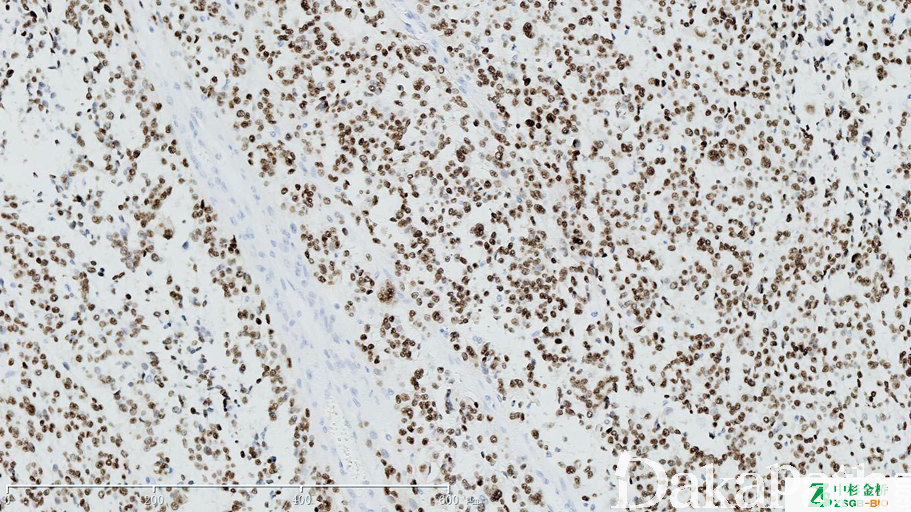

SOX10

转录因子,表达于色素细胞及肌上皮细胞的细胞核。

信号定位: 胞核